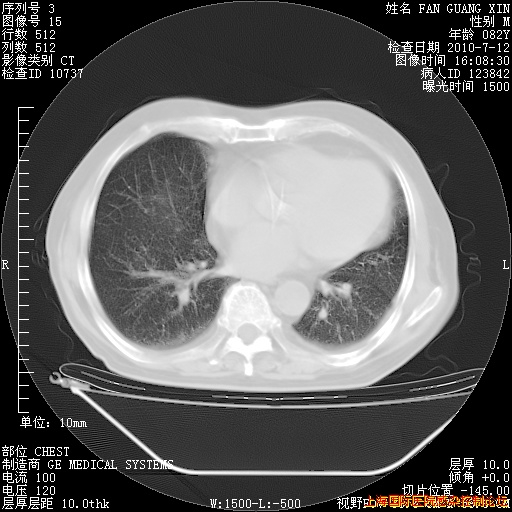

6月12日纵膈窗